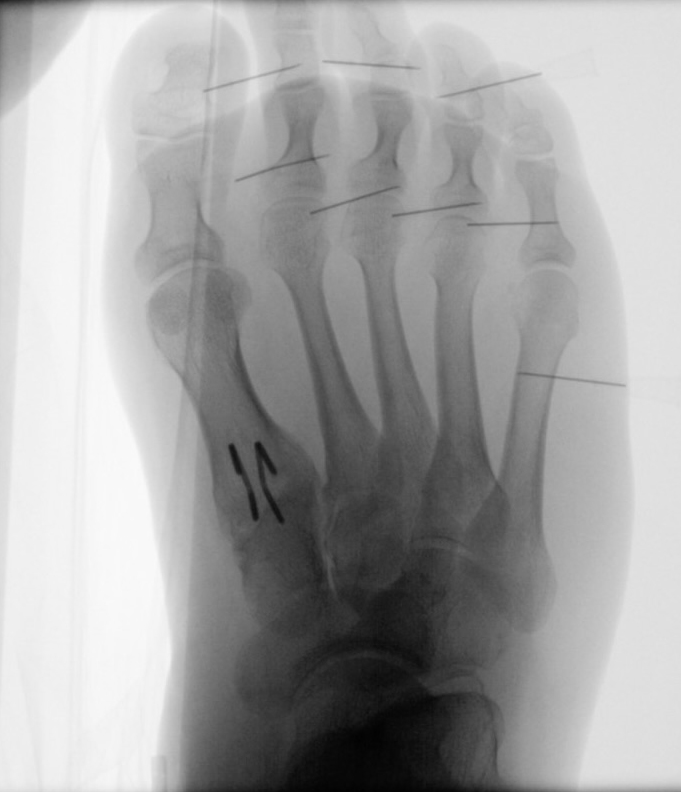

In der Regel bestehen aktive Wachstumsfugen bei Mädchen bis zum 12. und bei Jungen bis zum 14. Lebensjahr, mit Abweichungen von einem Jahr nach unten und nach oben. Präzise Informationen unter anderem darüber gibt das präoperative Röntgenbild (Abb. 2).

Abb. 2 a-c: offene Wachstumsfugen MT I Basis und Zehen (a), teilweise geöffnete Wachstumsfugen (b) und geschlossene Wachstumsfugen (c).

Zum Lesen der Bildbeschreibung und zur Vollansicht bitte die Bilder anklicken. Bilder: A. Helmers.